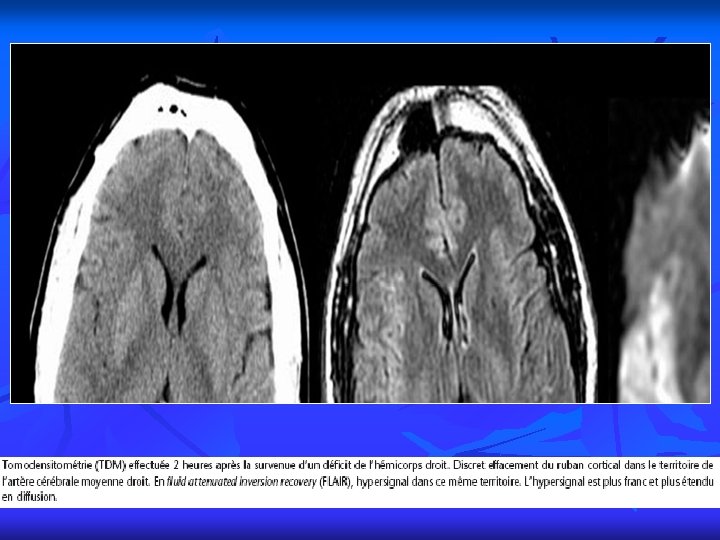

PRINCIPALES INDICATIONS 2 A Imagerie de diffusion perfusion Intérêt pour un bilan neuro-vasculaire mais aussi pour l’étude de la vascularisation des tumeurs cérébrales.